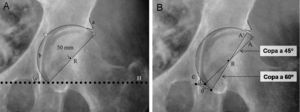

Posteriormente, se determinan la posición y el tamaño del componente acetabular utilizando las plantillas con magnificación adecuada. Mediante la superposición de las plantillas del componente acetabular se busca aquel tamaño que cumpla con las siguientes condiciones: copa con abducción aproximada de 45°, borde medial de ésta, aproximada a la línea ilioisquiática, borde inferior aproximado a la línea horizontal de referencia interlagrimal con el que se obtenga una máxima cobertura lateral ósea con mínima remoción de hueso esclerótico subcondral (fig. 2A). Tras la selección del tamaño y posición del componente acetabular se marca en la radiografía el centro de rotación y el perfil de la copa.

Plantillado del componente acetabular. A) La imagen muestra un componente acetabular de tamaño y posición adecuados. B) Imagen que muestra la utilidad de la distancia (d) entre el borde inferomedial del componente acetabular y el vértice inferior de la imagen en lágrima para determinar la inclinación acetabular precisa. La distancia (d) en una copa con una inclinación correcta (45°) aumenta a una distancia (d’) con el incremento de la inclinación del componente acetabular (A’ a 60° de inclinación). Por otra parte, con el incremento de la inclinación de la copa acetabular, reduciremos la cobertura lateral de la copa, que se ve reflejado en la menor distancia entre el vértice superior de la copa y el borde acetabular superoexterno. a: borde acetabular superoexterno; A: componente acetabular con inclinación correcta; A’: componente acetabular verticalizado; b: línea ilioisquiática; c: imagen en lágrima; d: distancia del componente acetabular correcto; d’: distancia del componente acetabular verticalizado; e: distancia entre el vértice superior de la copa y el borde acetabular superoexterno; H: línea horizontal de referencia; R: centro de rotación del componente acetabular.

Para lograr reproducir intraoperatoriamente la inclinación del componente acetabular planificado deben tomarse 2 medidas radiológicas con la regla magnificada. La primera es la distancia entre el vértice inferior de la copa dibujada y la imagen en lágrima (fig. 2B). Esta distancia suele ser corta (5–10mm) y muy sensible a los cambios de inclinación de la copa. La segunda medida es la distancia entre el vértice superior de la copa acetabular y el borde acetabular superoexterno.

El componente acetabular debe colocarse entre 40–50° de abducción29 y 15±10° de anteversión y el tamaño de componente acetabular planificado orienta el inicio del fresado del cotilo. Para reproducir de forma precisa la orientación del componente acetabular se utilizan las medidas de referencia registradas en la nota quirúrgica. Es necesario disponer de un instrumento fino milimetrado para calcular estas medidas debido a la profundidad y estrechez de la zona. Tras la colocación del componente acetabular de prueba en la posición adecuada, se palpa la imagen en lágrima (borde más inferomedial de la pared acetabular) con el instrumento fino y se mide la distancia entre este punto y el borde inferior del componente acetabular.

Si esta medida es mayor que la registrada durante la planificación, indica que el componente acetabular está más verticalizado30 y será posible corregir su posición (fig. 2B). Por el contrario, si la medida es menor que la planificada, indica que el componente acetabular está más horizontalizado. La reproducción de la distancia entre el vértice superior de la copa y el margen superoexterno del cotilo (cobertura lateral) confirmará la inclinación adecuada del componente.